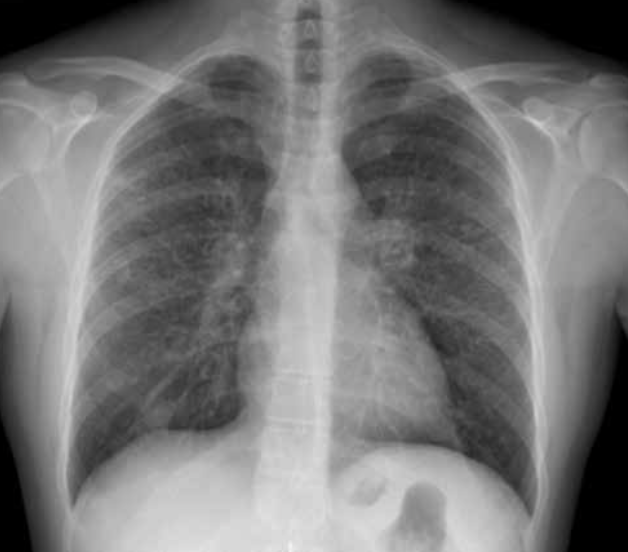

Rx normal.

Radiografía posteroanterior.

Es la proyección más utilizada. Convencionalmente se realiza en bipedestación, en inspiración profunda y a larga distancia para minimizar la magnificación.